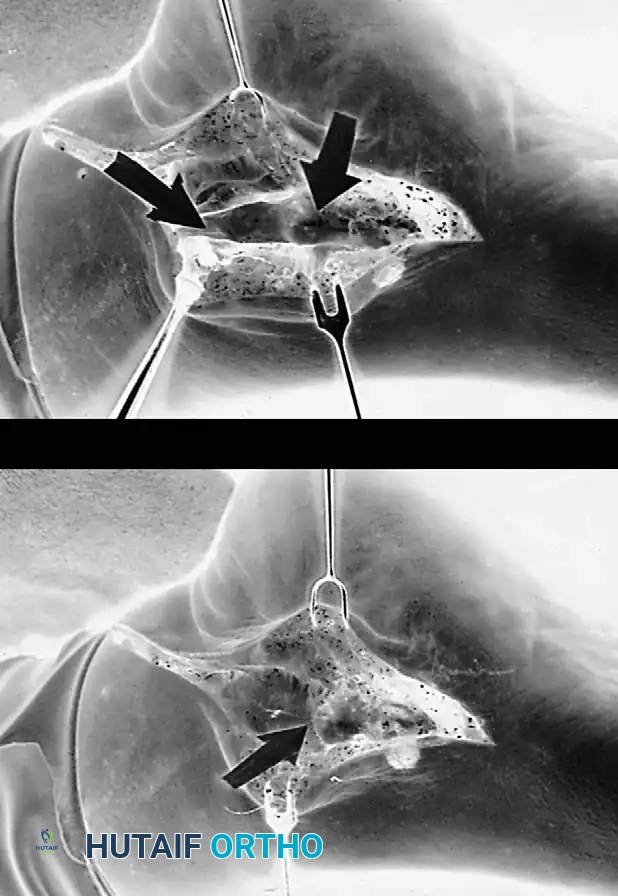

* Approach: A dual-incision technique is standard. A lateral incision over the sinus tarsi exposes the subtalar and calcaneocuboid joints. A medial incision exposes the talonavicular joint.

* Preparation: All articular cartilage is meticulously denuded down to bleeding subchondral bone using curettes and osteotomes.

* Correction: The deformity is corrected by manipulating the joints. The hindfoot must be fused in 0 to 5 degrees of valgus. Never fuse the hindfoot in varus.

* Fixation: Large cannulated screws are used for the subtalar joint (calcaneus to talus). The talonavicular and calcaneocuboid joints are fixed with screws or specialized locking plates.

Pitfall: Failure to adequately prepare the talonavicular joint is the most common cause of nonunion in a triple arthrodesis. Ensure aggressive decortication and rigid compression.